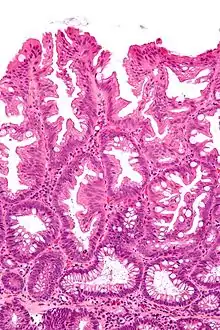

| Tubulovillous adenoma (tubular component – left of image, villous component – right of image). H&E stain. | |

Tubulovillous adenoma

Tubulovillous adenoma, TVA are considered to have a higher risk of becoming malignant (cancerous) than tubular adenomas.[9]